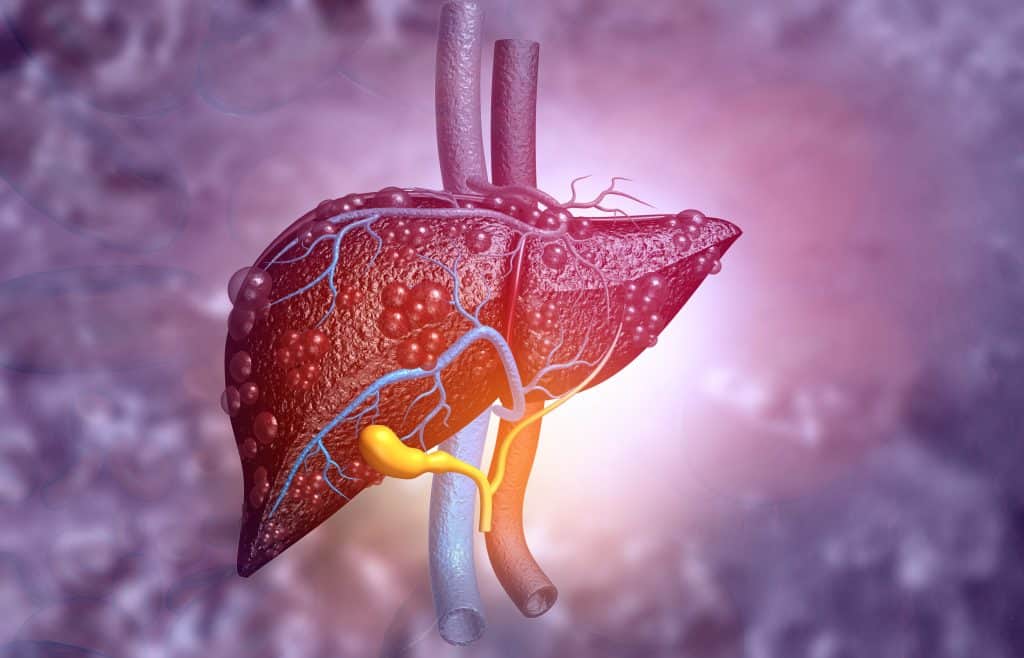

Jetra je izrazito važan organizam u ljudskom tijelu te je jedna od njenih glavnih zadaća detoksikacija organizma. Osim detoksikacije organizma, neke od njenih zadaća su proizvodnja žući za olakšavanje probave, stvaranje proteina, služi za spremanje željeza, potiče stvaranje tvari koje pomažu zgrušavanju krvi te filtrira i uklanja bakterije, kao i toksine iz organizma kako bi imunitet bio u što boljem stanju.

Kako bi jetra uspješno odrađivala svoj posao, važno je da je funkcionalna i zdrava, no kako je ona tzv. "tihi organ", bolesti i oštećenja se najčešće otkriju tek kad problemi uznapreduju. Jedan od najčešćih problema vezanih uz jetru je bolest masne jetre, odnosno, stručno nazvano steatoza. Uzrokuje je preveliko nakupljanje masti na području jetre te s vremenom ta bolest može usporiti funkcioniranje jetre. Prirodni lijek za masnu jetru dobro je znati kako bi sami djelovali i liječili te probleme. Iz tog razloga ćemo u nastavku teksta navesti koji je to prirodni lijek za masnu jetru kako bi vaša jetra bila ponovno zdrava.

Bolest masne jetre javlja se i napreduje kroz tri faze. Prva faza je kada se u jetri nakupljaju velike količine masti što uzrokuje naticanje, odnosno, upalu jetre te se zbog toga nastavlja nakupljati mast. Druga faza je da na jetri dolazi do stvaranja ožiljaka, no jetra i dalje zadržava svoju funkciju. Ukoliko se upala i ožiljci ne uklone, bilo liječnikom intervencijom ili da se uzima prirodni lijek za masnu jetru, dolazi do toga da ožiljci i čvorići krenu zamjenjivati zdravo tkivo što rezultira cirozom te govore o uznapredovaloj bolesti jetre. Masna jetra razlikuje se po tome da li je nealkoholna ili alkoholna.